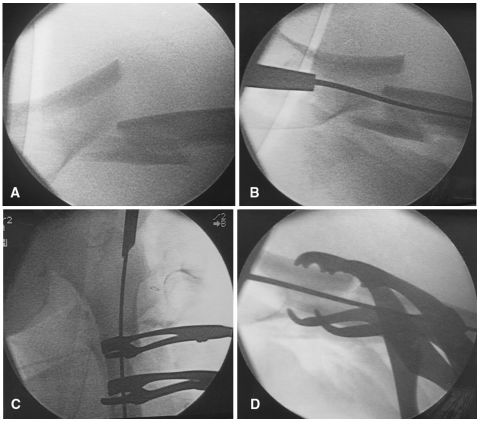

对于复杂的粗隆下骨折和闭合复位不可行或不能接受的骨折,应使用切开复位技术。在这种情况下,为了保存骨折生物学,建议采用微创复位技术。单皮质Schanz钉可以通过皮肤的穿刺切口使用,以便操纵骨折碎片。一个或两个Schanz钉可以通过电钻置入在想要进行复位的骨折块中,并与T形手柄连接用作操纵杆,从而使外科医生能够操纵骨折碎片以获得满意的复位和推进导丝。在进行扩髓之前,应该用C臂机透视检查评估Schanz钉辅助下的骨折复位情况和Schanz钉所处的位置(如图2A-C所示)。这项技术几乎是无创的,可以在扩髓过程和置入髓内钉的过程中保持复位。

图2 A经皮Schanz钉微创复位治疗股骨粗隆下横形骨折;C将Schanz针插入到近端骨折块;C将另一针插入到远端片段以便于复位

球钉推进器、骨钩或Hohmann拉钩等器械可用于直接复位骨折,方法是在骨折处作辅助切口,并钝化剥离骨折部位的筋膜。必须战略性地选择器械的位置,以便进行适当的节段处理(如图3a-c所示)。如果使用球钉,建议用2.7mm钻头在骨头上打一个小的单皮质孔,以避免器械滑动和移位。在典型的股骨粗隆下骨折中,远端骨折是内收的,用骨钩进行外侧牵引远端骨折块可能有助于复位。在这种特殊的情况下,需要一个大约3~4厘米的辅助切口,钩子应该从后面通过到远端骨折的内侧。然后,外科医生可以外展并抬高远端片段,以实现骨折充分复位和导丝的通过(如图4A,B所示)。类似地,可以用骨钩复位近端骨折,然后用复位骨夹固定(如图5a-c所示)。对于复杂粉碎性骨折,通过同一切口,可以用柯克氏钳操作骨折块(如图6A,b所示)。

图3 A(正位)和B(侧位)C臂机透视下显示使用Hohmann牵引器进行股骨粗隆间骨折微创复位;C在整个手术过程中,Hohmann牵引器一直固定在适当的位置

图4 A(正位)和B(侧位)C臂机透视下显示使用骨钩进行股骨粗隆间骨折微创复位